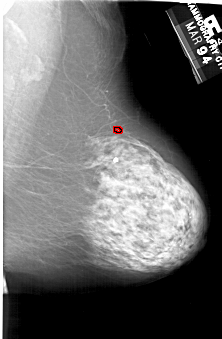

A_1829_1.RIGHT_MLO

RIGHT_MLO LINES 6436 PIXELS_PER_LINE 4201 BITS_PER_PIXEL 12 RESOLUTION 43.5 OVERLAY

FILE: A_1829_1.RIGHT_MLO.OVERLAY

TOTAL_ABNORMALITIES 1

ABNORMALITY 1

LESION_TYPE CALCIFICATION TYPE PLEOMORPHIC DISTRIBUTION CLUSTERED

ASSESSMENT 4

SUBTLETY 3

PATHOLOGY BENIGN

TOTAL_OUTLINES 1

BOUNDARY